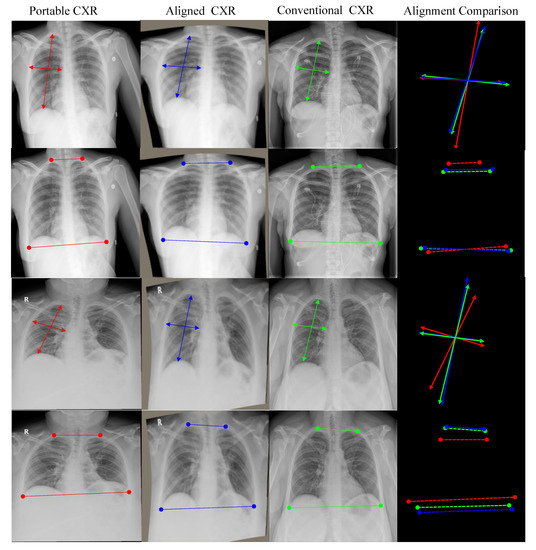

4.3.1. CXR Alignment Network

- Secondly, we introduce a new deep learning-based approach to align a subject-pairs dataset to obtain pixel-pairs dataset. In order to learn the knowledge correlation between two different domains, it is important to have a pixel-wise pair dataset. Thus, alignment is an important step that helps to perform knowledge transferring from the source domain to target domain.

| Portable CXR vs. Conventional CXR | Aligned CXR vs. Conventional CXR | |

|---|---|---|

| Left Lung | 203.03 | 42.02 |

| Right Lung | 239.31 | 38.86 |

| Entire CXR | 221.17 | 40.44 |